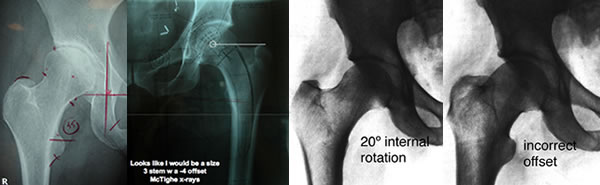

Hundreds of x-rays were review both in Australia, Canada and the United States. Participating in this process acknowledgment goes out Doctors Peter Hannaford, John Harrison, Allen Turnbull, Ian Woodgate of Australia, Hugh U. Cameron, of Canada, Louis Keppler, John Keggi, Kristaps J. Keggi, Robert Kennon, and S. David Stulberg from the United States.